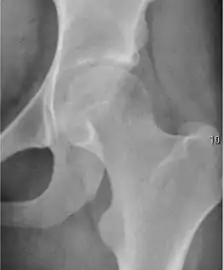

Plain radiography allows us to categorize the hip as normal or dysplastic or with impingement signs (pincer, cam, or a combination of both). Besides these, pathologic processes like osteoarthritis, inflammatory diseases, infection, or tumors can also be identified (Figure 1).[1]

Figure 1.

Radiography in normal hip